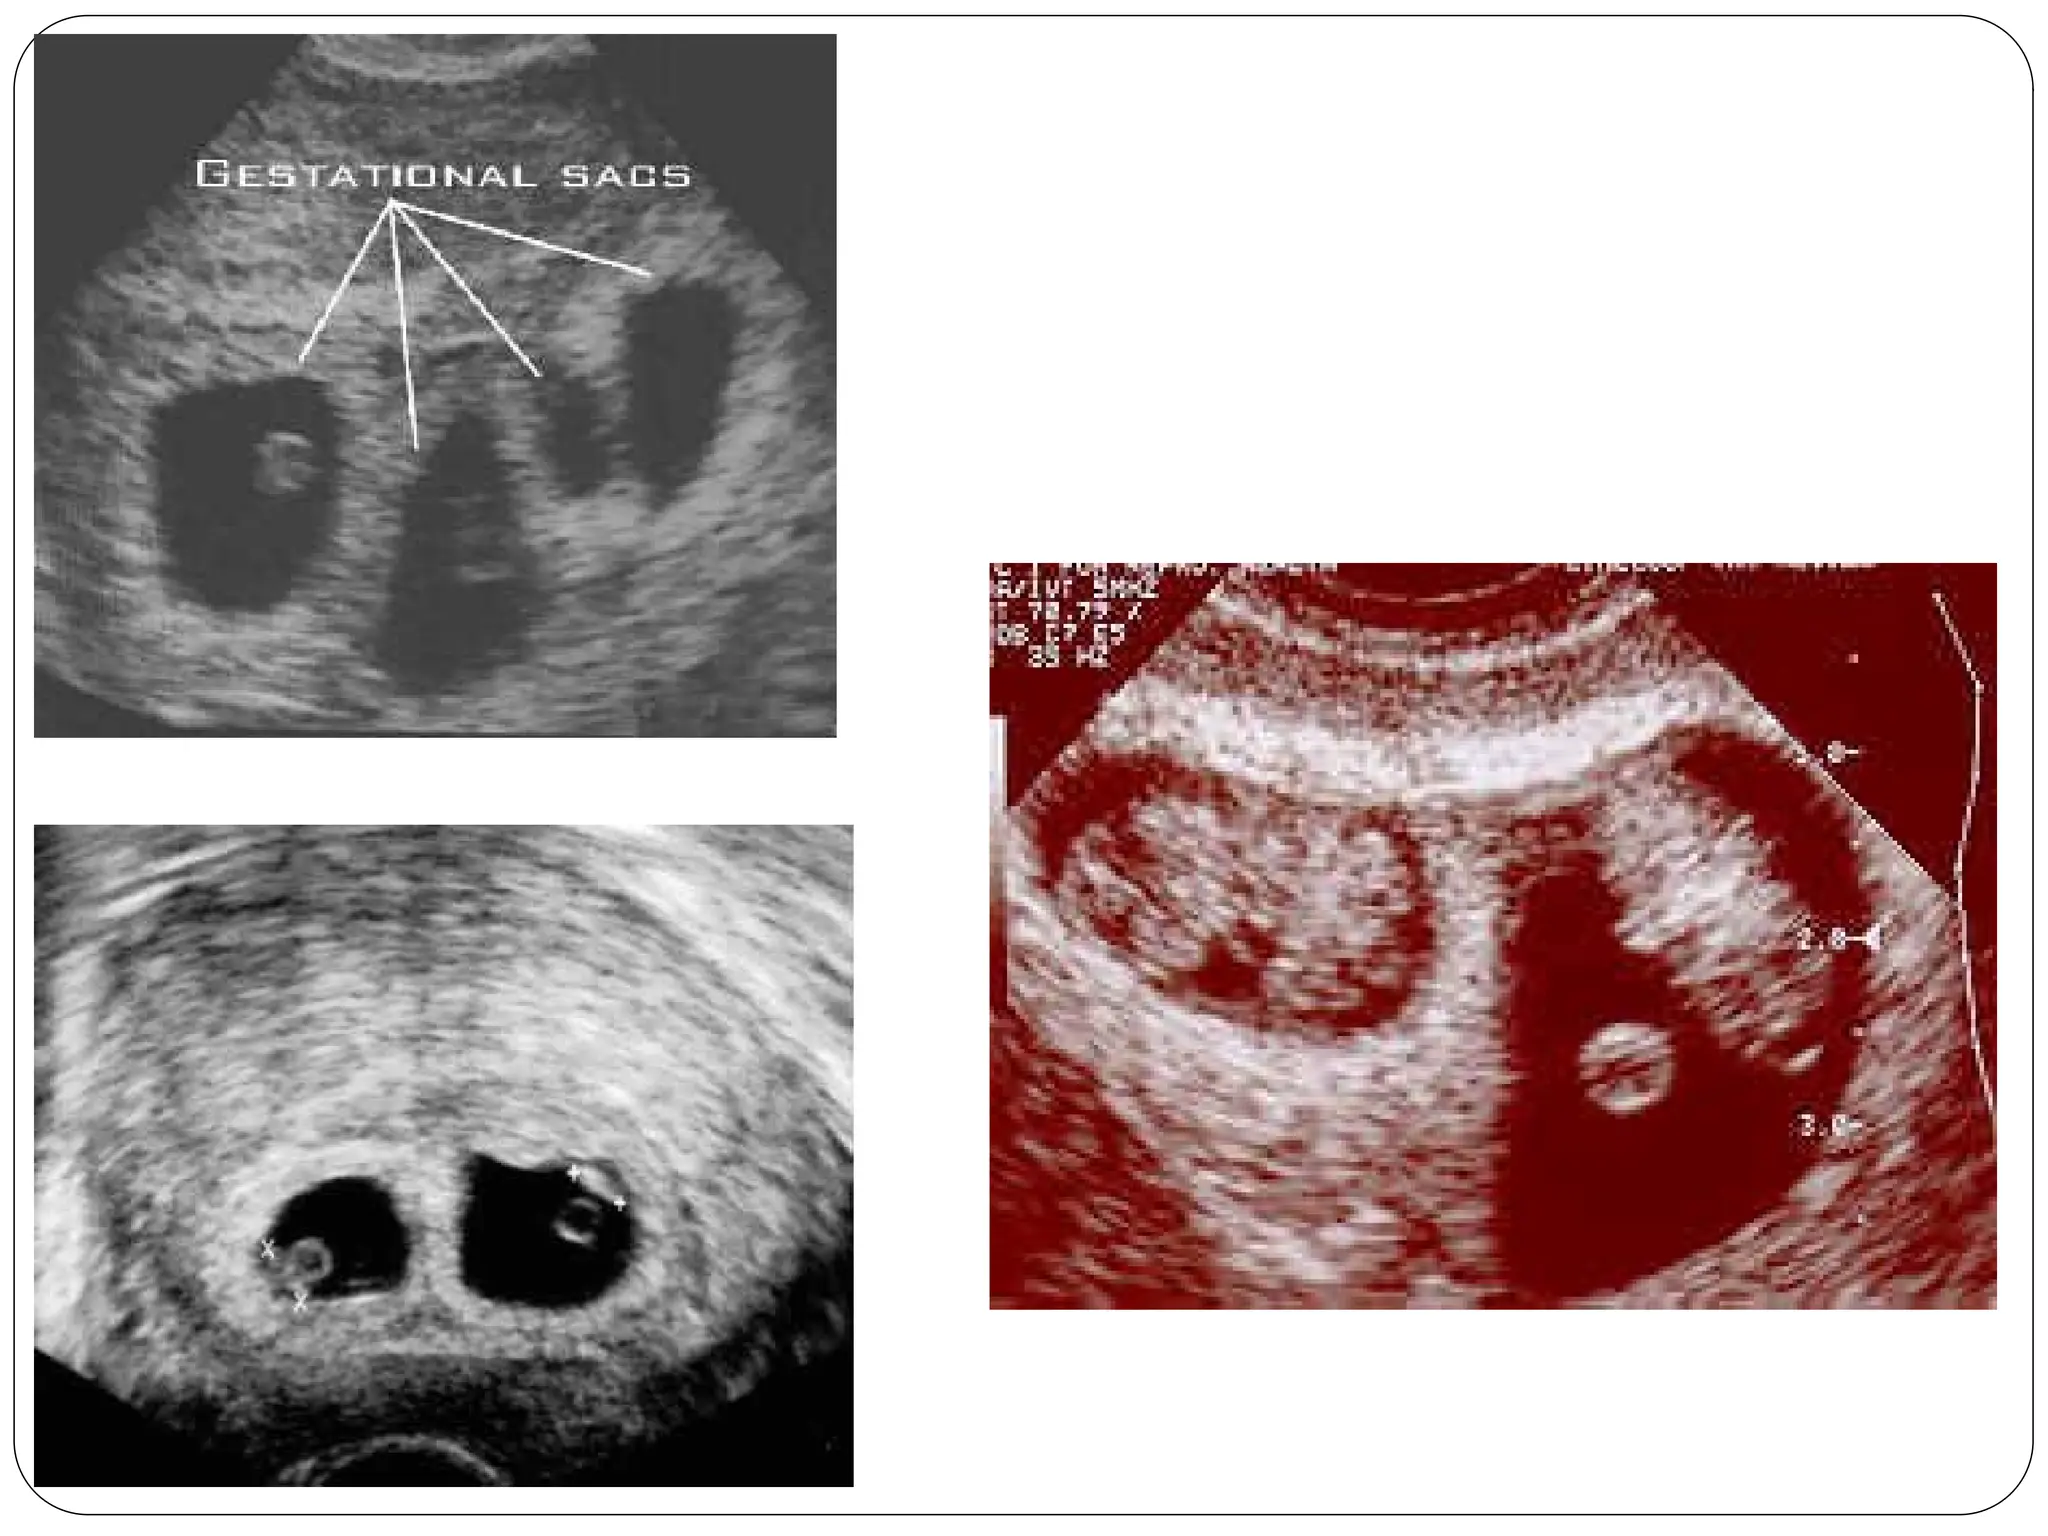

Multiple Pregnancy

DEFINITION

When more than one fetus

simultaneously develops in the

uterus ,it is called multiple

Twins (most common)

Monozygotic Twins…

Dizygotic twin pregnancy

Di-chorial and Di-amniotic.

Dyzygotic twins, are descended from a double ovulation and a double fertilization.

The 2 eggs are completely independent.

This configuration represents two thirds of all twin pregnancies.

Vanishing twins

USG in early pregnancy revealed occassional

death of one fetus and continuation of

pregnancy with surviving one